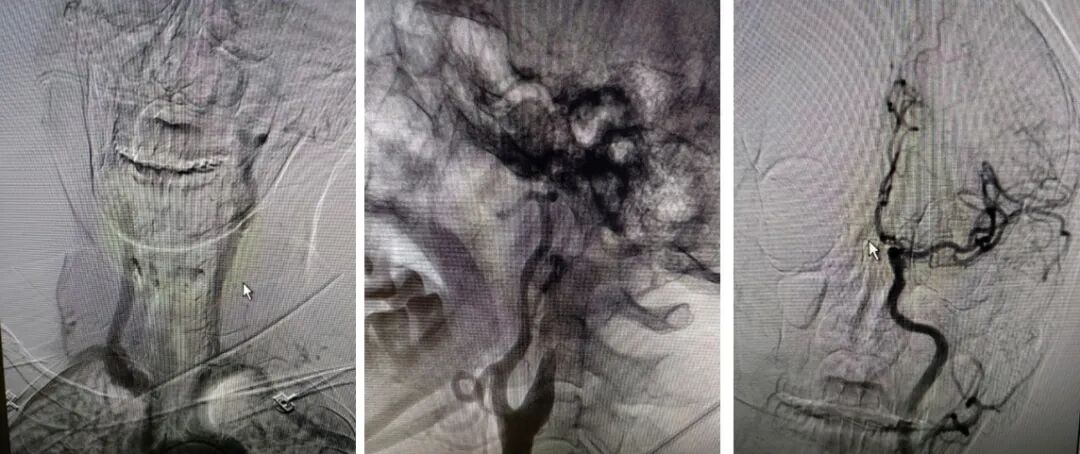

重要影像结论:右侧ICA起始部急性闭塞,前交通动脉、后交通动脉未开放。

6F-远端通路导管在黑泥鳅导丝的指引下通过闭塞段送至眼动脉段,造影证实闭塞段在海绵窦段,予以ADPAT技术取出少量血栓,仍未开通。

通过微导管释放取栓支架,SWIM取栓技术,可见海绵窦段狭窄,前向血流不稳定。

利用PTA球囊导管对狭窄处进行扩张,可见狭窄明显改善,但眼动脉段以后闭塞,再次将取栓支架予以取栓,可见斑块逃逸至M1段。